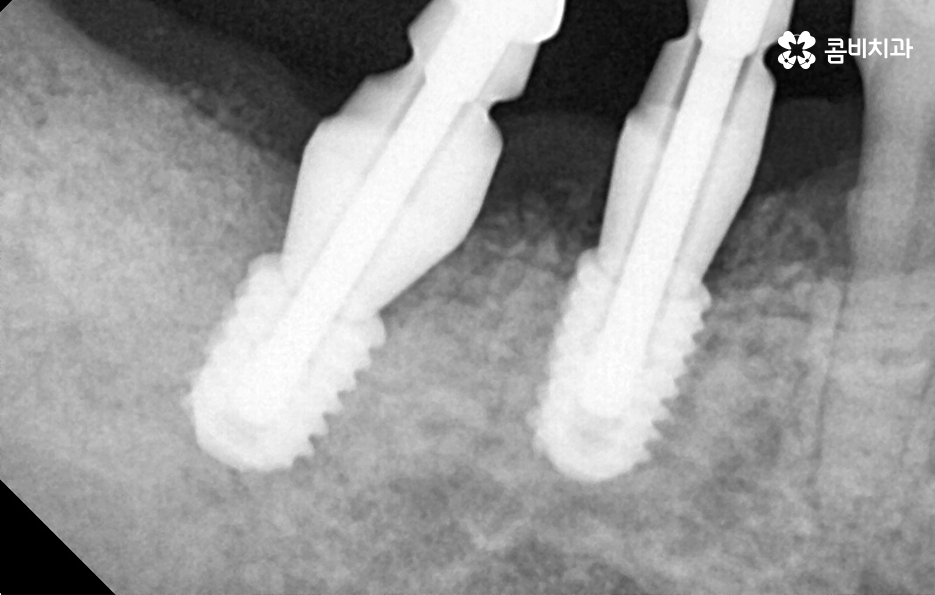

치주염으로 인해 치아를 잃게 되신 분들은 잘 아시겠지만 잇몸이 퇴축되어 있고 잇몸 뼈가 부족하여 임플란트 치료 과정 상에 뼈이식이 필요한 경우가 많고 치아를 한꺼번에 여러 치아를 잃게 되어 임플란트를 여러 개 심어야 하는 경우도 많을 거예요

잇몸 뼈가 부족한 경우 뼈이식을 통해 임플란트를 식립하기 좋은 잇몸 상태를 만드는 것이 치료 결과에도 중요하며 임플란트의 식립 위치부터 각도, 깊이 등은 치과의 첨단 장비뿐 아니라 치과의사의 경험과 실력이 중요한 부분이기 때문에 임플란트의 전체 과정을 고려하여 비용도 중요하지만 건강한 치료 결과를 위해 종합적으로 따져보고 치과를 선택하시길 권하고 있어요